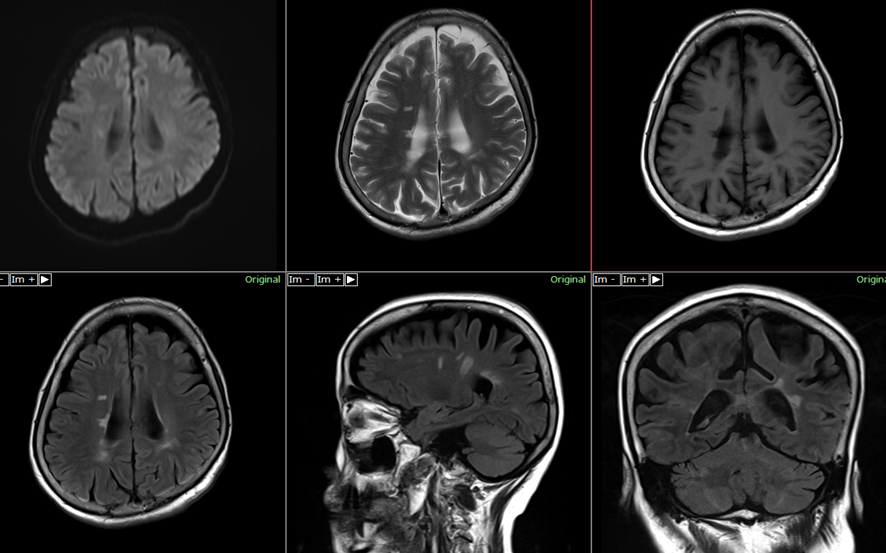

研究により、MS患者の脳の白質と灰白質に変化があることが判明しました。しかし、医師がMRIスキャンを通じて検出する構造的損傷と認知機能障害の症状との間に明確な関連性はありません。